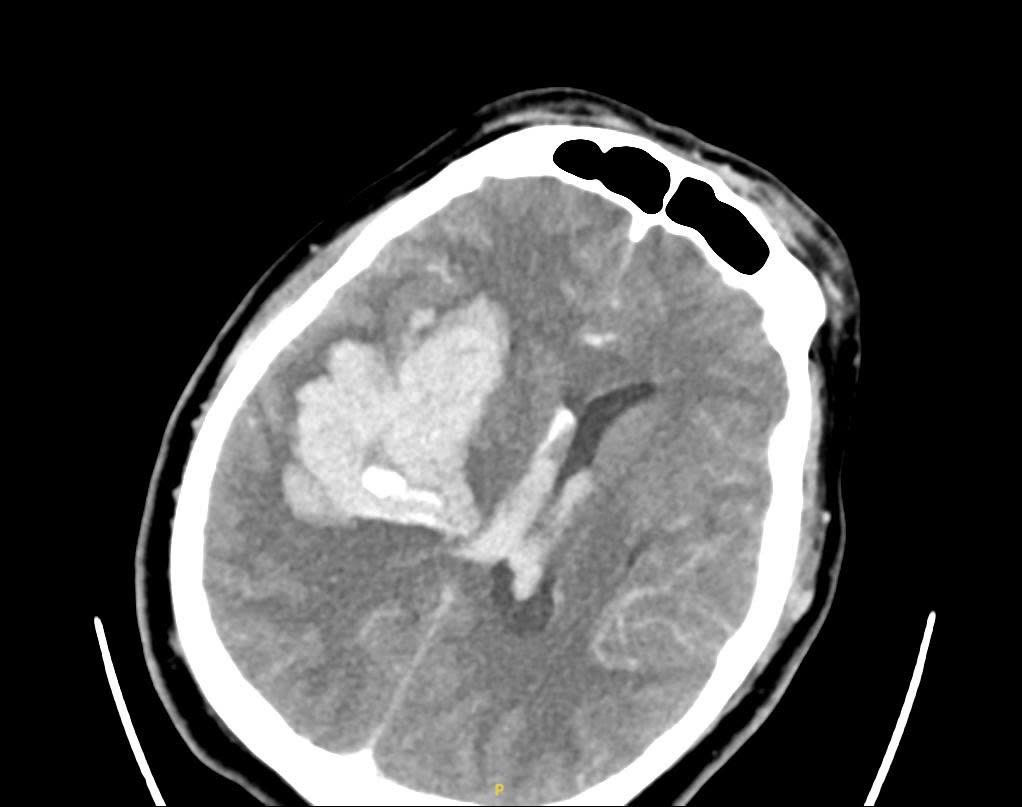

Kết quả CT não cho thấy ông V. bị xuất huyết não diện rộng. Bệnh nhân được đặt nội khí quản để bảo vệ đường thở và chuyển mổ cấp cứu ngay lập tức. Trong quá trình đặt ống nội khí quản, bác sĩ hút ra rất nhiều nước cốt chanh và cả cặn thuốc đọng trong họng. Nguyên nhân do người nhà cho bệnh nhân uống chanh, thuốc và chất lỏng tràn vào đường thở, làm người bệnh nguy kịch nhanh hơn. Sau một ngày cấp cứu, hiện bệnh nhân vẫn phải nằm hồi sức tích cực.